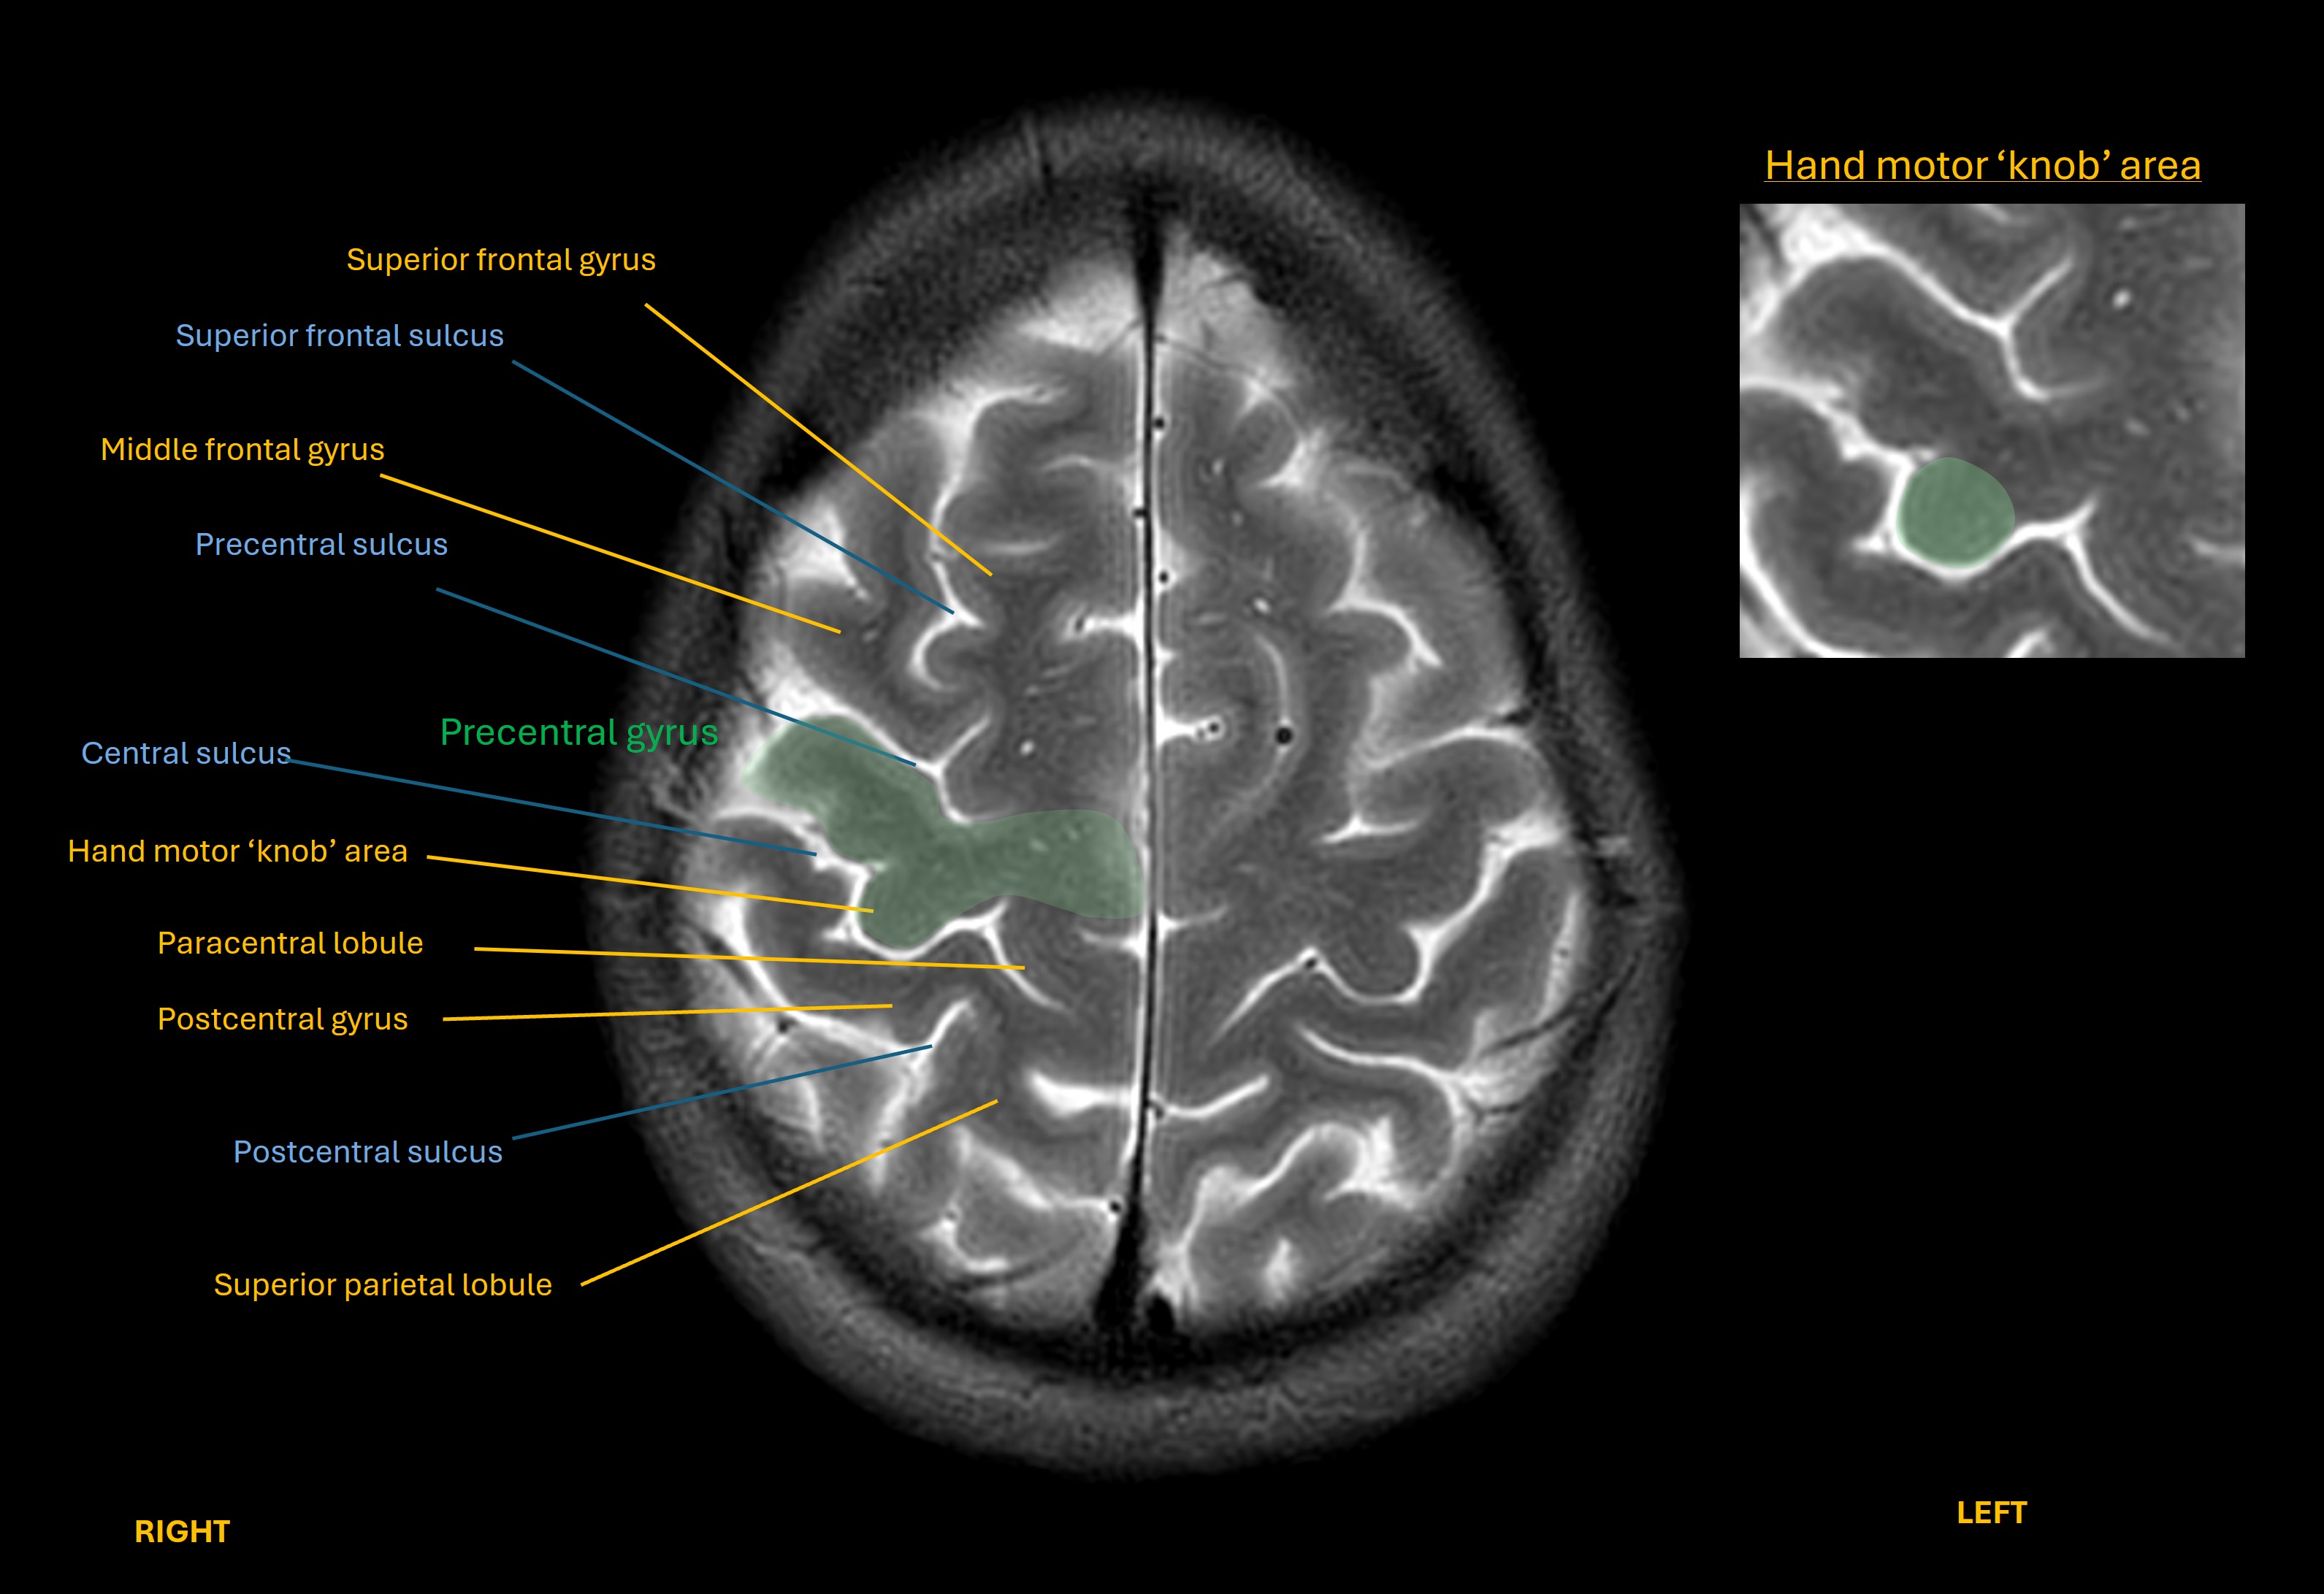

Given its importance, and the complicated hand functions we can make with the dozens of muscles involved, there is a distinct area of the motor cortex (precentral gyrus) dedicated to it, visible on axial imaging as a ‘knob’.

Motor hand knob area

Lesions in the this area of the cortex (such as a stroke) can paralyse the hand – but the pattern is global hand muscle weakness. A lesion here would not selectively spare some of the finger movements this patient is still able to make such as flexion and abduction.